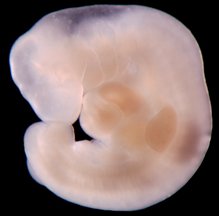

And the photograph below is a textbook photo so you can see the detail: